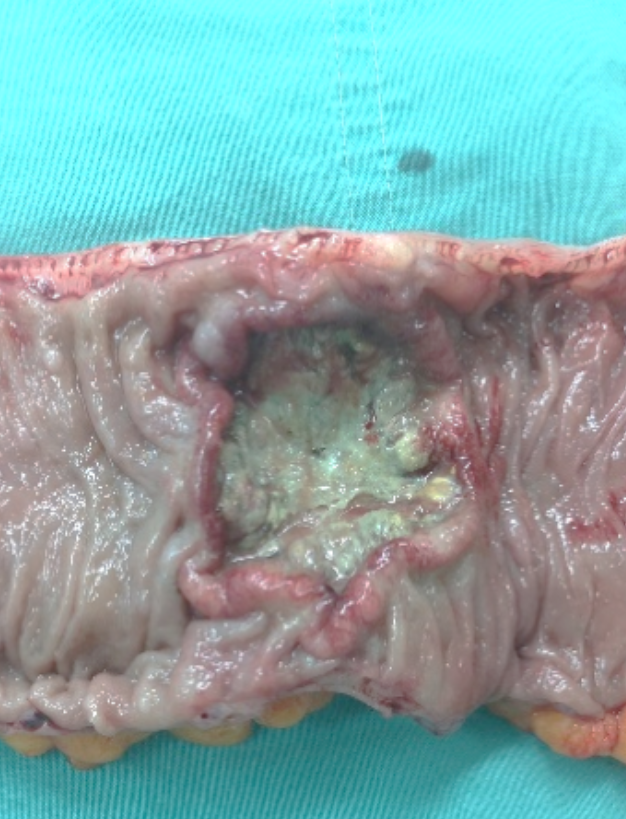

切开标本可见一菜花样肿物.临床诊断为升结肠癌.

下图二:切除标本剖开照:结肠菜花样肿瘤,直径6厘米.